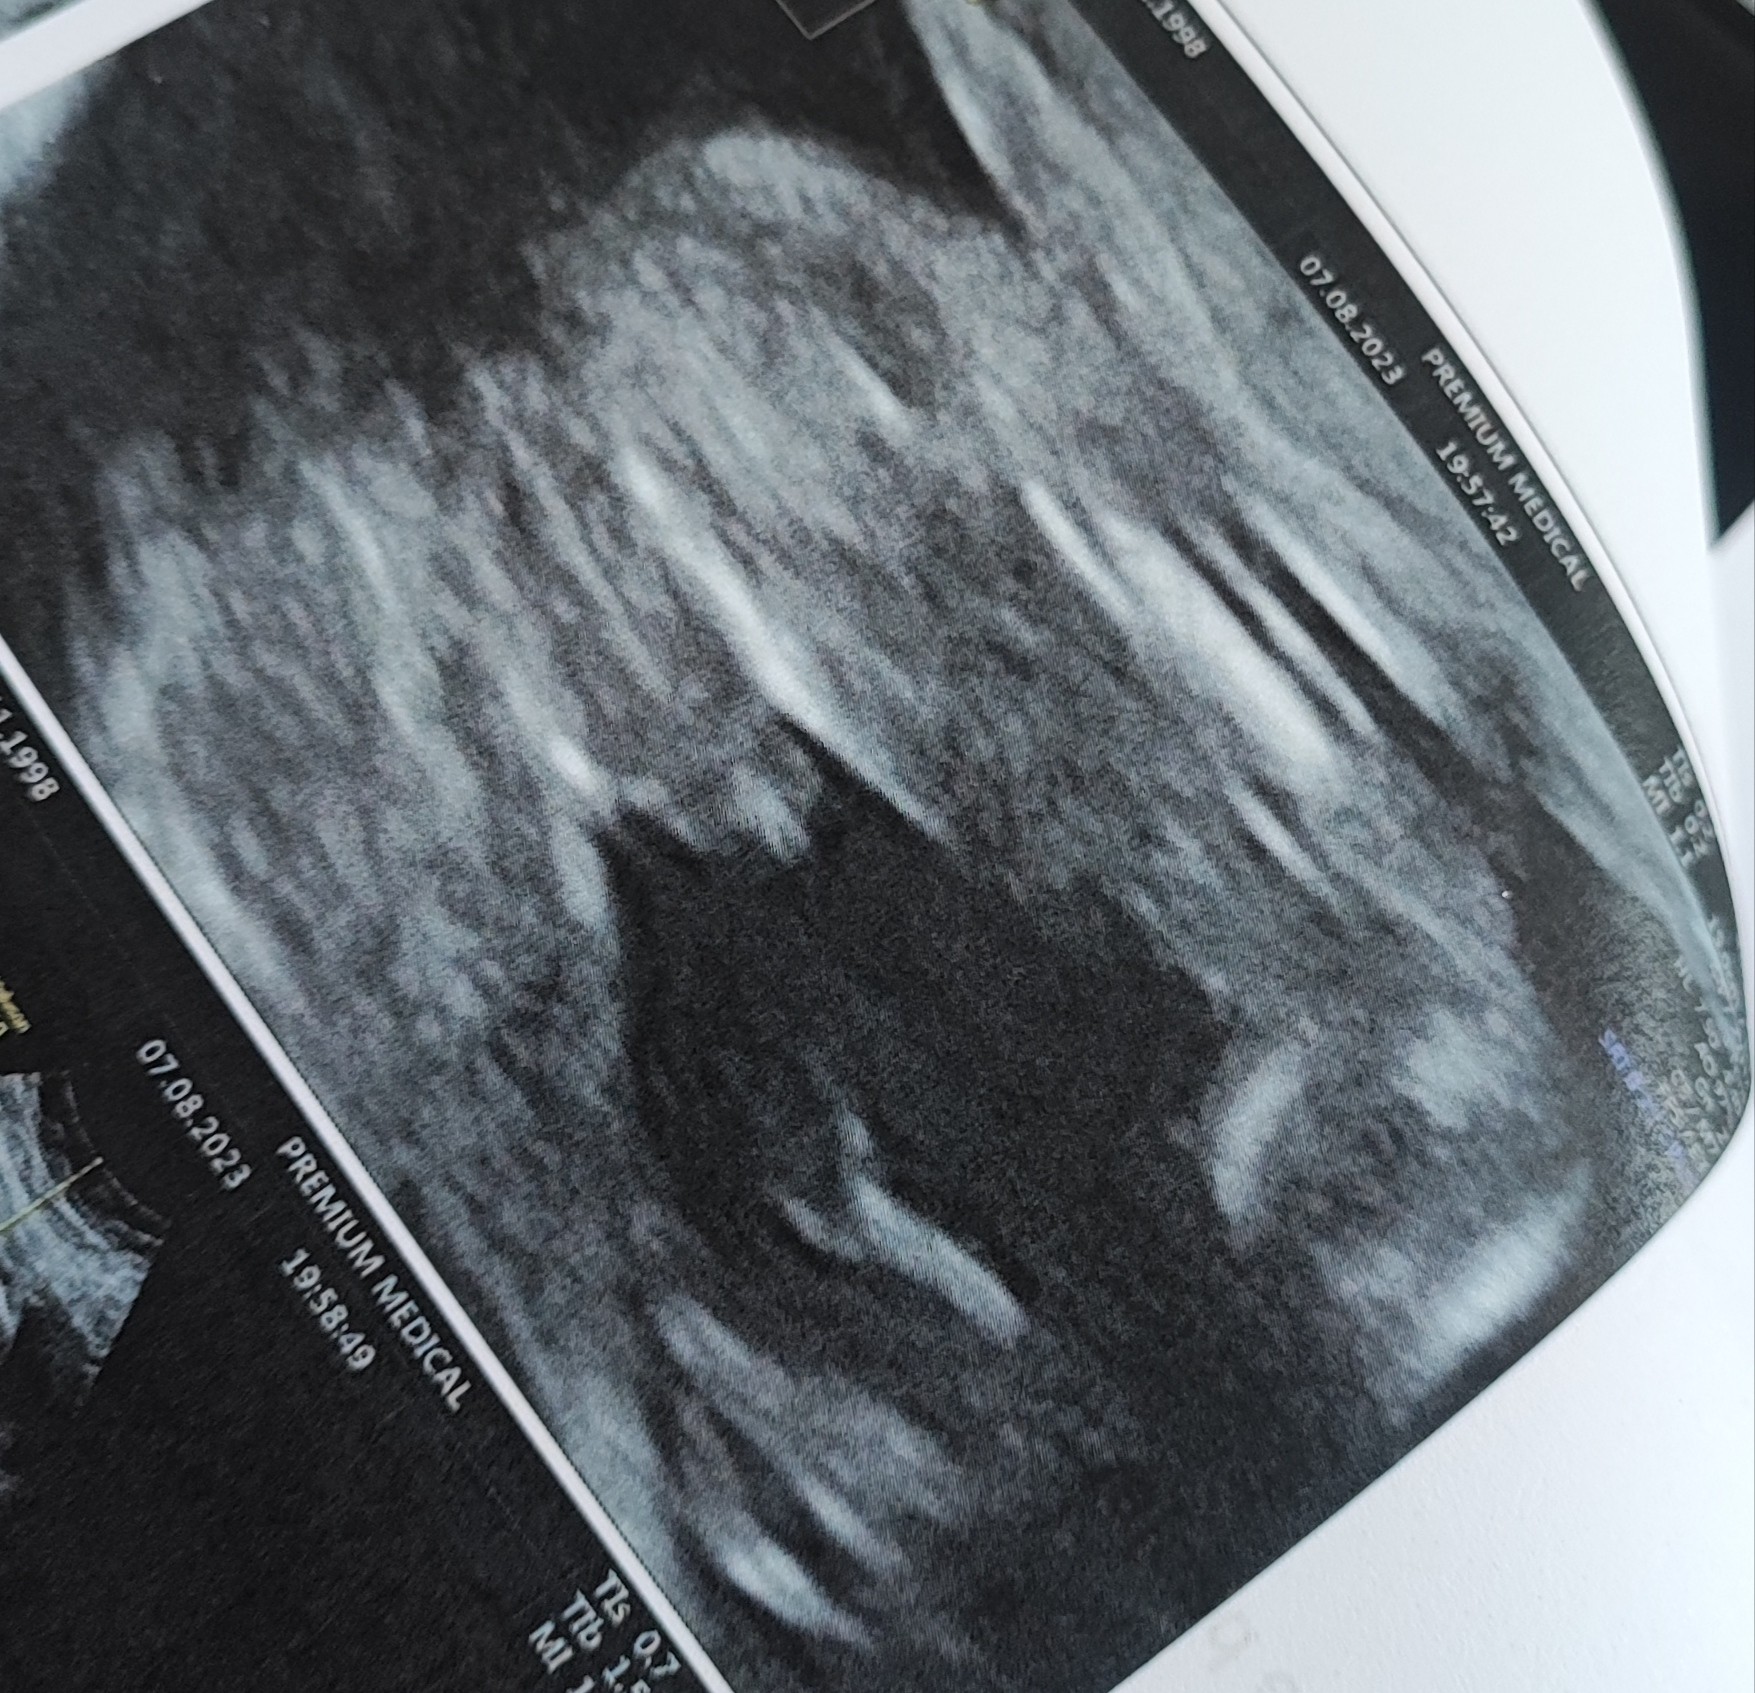

Jak myślicie chłopiec czy dziewczynka? 21+1

Widac dokładnie moszne i cycusia .

Cycusia?Widac dokładnie moszne i cycusia .

PENISA … lepiej ?Cycusia?

Oczywiście, że lepiej. Nazywajmy rzeczy po imieniu. Cycuś to cycuś a penis to penis.PENISA … lepiej ?